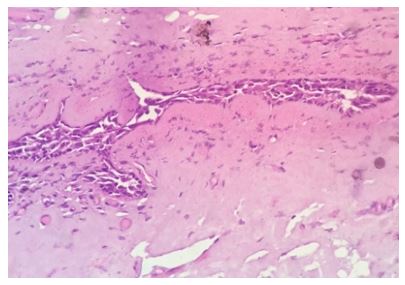

She had pre-operative ultrasound scan of the breast which showed a round hypo-echoic lesion (see figure 2). Histopathology examination of the excised specimen showed a cyst that contained folds of laminated chitinous layer which was partly lining the wall of the cyst and the encompassing areas did show chronic inflammation with sheets of foamy macrophages (see figures 3 and 4). The microscopic examination of the specimen also showed foreign body giant cell reaction as well as occasional ill-formed granuloma and the surrounding normal breast tissue was also visualised (see figures 5 and 6). She was sent for further treatment.